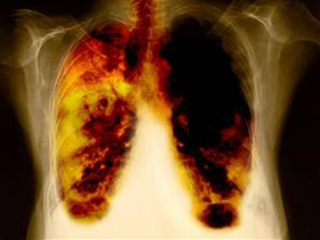

癌症是人类最大的敌人,特别是肺癌,发病率非常高。那么有什么方法可以预防肺癌呢?肺癌的早期症状有哪些?下面小编马上来详细的分析女性患上肺癌的早期症状有哪些,来详细看文章吧......